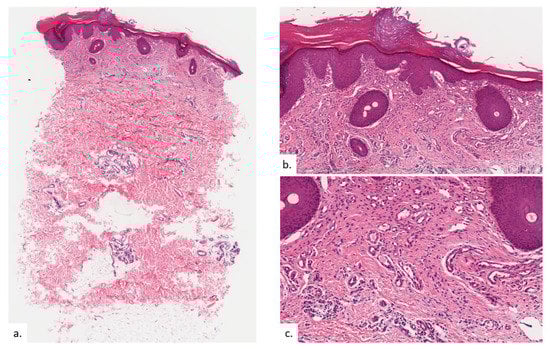

Figure 2.

Patient 1. (a,b) There was hyperkeratosis with psoriasiform hyperplasia; (c) there was prominent vascular proliferation present in the upper to the mid dermis, consisting of proliferation of capillary type vessels without any overt endothelial cell atypia; (d) a modest increase in lymphatic channels was highlighted on podoplanin; (e,f) MC density was increased in proportion with vasoproliferation as seen on CAE stain.